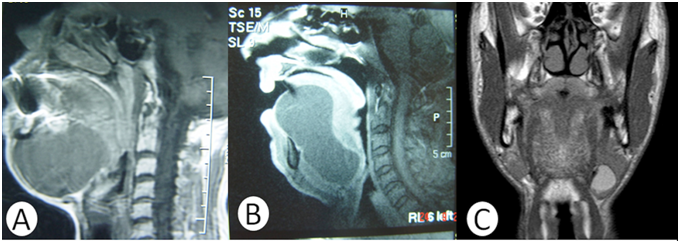

The mean age for the patients was 32, and the age range was between 1 to 64years. Male to female ratio was 4:3. The initial complaint was painless swelling below the tongue in five patients and below the jaw in two patients. Other symptoms included difficulty in swallowing and speech for three of the patients. Bimanual palpation showed a soft and limited mass in all patients. Locations of the cysts were submental in one patient (14%), submandibular in one patient (14%), both sublingual­-submental in one patient (14%), and sublingual in four patients (57%) (Figure 1). On MRI, the cysts were observed in the floor of mouth (Figure 2). The cysts were observed hypointense in T1 weighted images, and hyperintense in T2 weighted images. The excision operations were performed by extraoral approach in two patients (median submental incision and left submandibular incision), and by intraoral approach in four patients (Figure 3&4). Demographic data, symptoms, location of the cysts, and the surgical approach used for treatment are given in Table 1. There were no complications in operations. In the histological examination of seven cysts, the cyst lumen was surrounded by numerous stratified keratinized squamous epithelium infiltrated by fibro vascular stroma that were rich in lymphocytes. The histopathologic examination of the cysts identified them as dermoid cyst. No recurrences were observed in any of the patients during the follow-up at 18 months.

Figure 2 On the MRI, sagittal section with T1 weighted of first patient showing the hypointense cyst above the mylohyoid muscle (A). Sagittal section with T1 weighted of the second patient showing the hypointense cyst bulged into submental region through the mylohyoid and the geniohyoid muscles (B). Coronal section with T1 weighted of fifth patient showing into submandibular region (C).